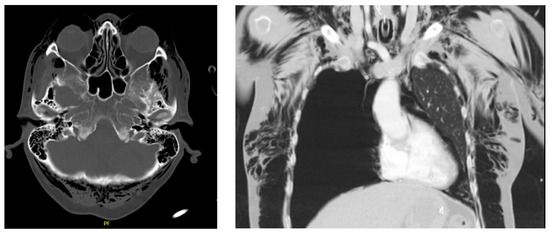

A 63-Year-Old Female Presenting to the Emergency Department with Massive Facial Swelling and Dyspnea

Diagnosis: Subcutaneous Emphysema